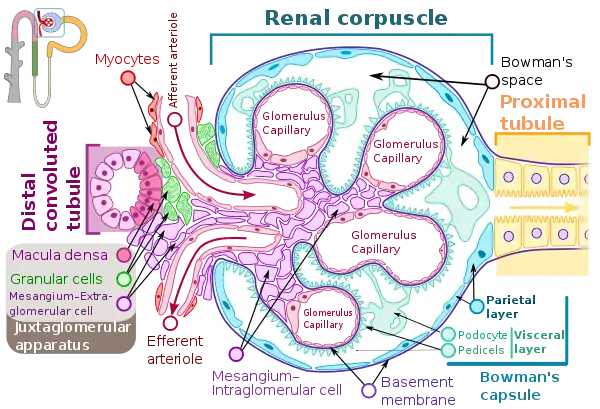

In DPGN Most of the glomeruli show endothelial and mesangial proliferation, affecting the entire glomerulus, leading to diffuse hypercellularity of the glomeruli, producing in some cases epithelial crescents that fill Bowman's space. When extensive, immune complexes create an overall thickening of the capillary wall, resembling rigid "wire loops" on routine light microscopy. Immune complexes can be visualized by staining with fluorescent antibodies directed against immunoglobulins or complement, resulting in a granular fluorescent staining pattern. Electron microscopy reveals electron-dense subendothelial immune complexes (between endothelium and basement membrane). In due course, glomerular injury in DPGN gives rise to scarring (glomerulosclerosis). Most of SLE patients with DPGN have hematuria with moderate to severe proteinuria, hypertension, and renal insufficiency.[2]

The etiology plays a role in the specific mechanism of DPGN. Usually the deposition of immune-complexes (antigen-antibody complex) that activates the complement system are involved.[4] The antibodies that form immune complexes deposits or they bind directly to the nonglomerular antibodies present. Immune-complexes are combinations of DNA, anti-dsDNA ubiquitin, and other proteins in DPGN that are associated with lupus nephritis. C1q, the first component of the complement system, encounters conformational change that leads to C3 convertase breaking C3 into C3a and C3b. C3a, C5a, IL-8 are all chemotactic factors of the activated complement system. Part of their role is to recruit polymorphonuclear cells and leukocytes. Interleukins like IL-6, tumor necrosis factor-alpha, and interferon-gamma, that cause cell injury, are released. Mesangial proliferation is caused by activated platelets.[7] Another mechanism involves antibodies formed against alpha-3 chain of collagen IV. Their deposition occurs in the sub-epithelial spaces. This causes proteinuria by damaging the basement membrane and creating a loss of negative charge. These are anionic deposits that fail to cross the membrane.[4]

Cationic deposits that cross the membrane are then deposited into sub-epithelial spaces. Then the disease advances and crescents are formed. Crescents are a combination of epithelial cells, activated macrophages, and fibrin. They lead to rupturing of small blood vessels, ultimately causing necrosis and sclerosis.[4]

The glomeruli are the filters in the kidneys. When working normally they will move the waste, excess electrolytes, and unnecessary fluid from the bloodstream to the urine.[8] When a person develops DPGN, over 50% of the glomeruli (diffuse) become inflamed. There is also an increase in mesangial, epithelial, and endothelial (proliferative) cells. Inflammatory cells are also rapidly developed.[9] This causes damage to the kidneys and does not allow for proper filtration.